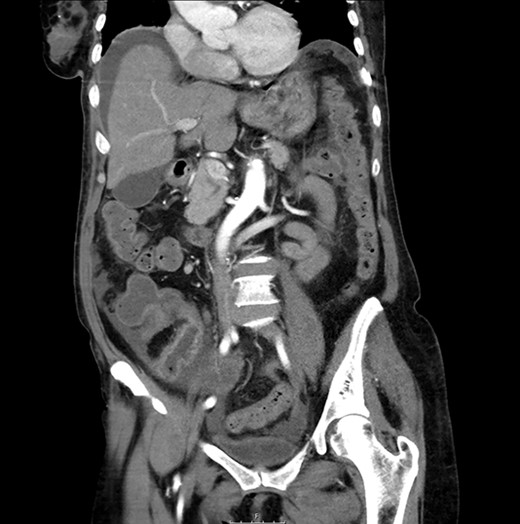

Abdominal X-ray: generalized dilatation of the small intestine without distal air in the colon or the rectum.

CT scan: sudden change of caliber at the terminal ileum together with signs of intestinal suffering.

An urgent laparotomy exposing the terminal ileum was performed, signs of intestinal suffering were evident in relation with a thickening and a retraction of the mesoileum at the terminal ileum responsible for the small bowl obstruction. An ileocecal resection with immediate side-to-side ileocolic anastomosis was performed (Fig. 3). Microscopic pathological examination: abundant calcium polystyrene sulfonate crystals along the intestinal wall surrounded by intense inflammatory infiltrate (Figs 4 and 5).